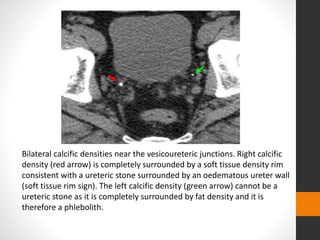

Bilateral calcific densities near the vesicoureteric junctions. Right calcific

density (red arrow) is completely surrounded by a soft tissue density rim

consistent with a ureteric stone surrounded by an oedematous ureter wall

(soft tissue rim sign). The left calcific density (green arrow) cannot be a

ureteric stone as it is completely surrounded by fat density and it is

therefore a phlebolith.